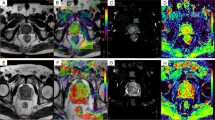

Comparisons of ADC values among the noncancerous PZ areas, BPH and each GS group are shown in Fig. 3. There were significant differences between the noncancerous PZ group and each GS group and between the BPH group and each GS group (p < 0.05). There were also significant differences between the noncancerous PZ areas and the BPH group (p < 0.05). Example cases of Pca lesions with GS-7 and GS-9 are shown in Figs. 4 and 5, respectively.

Pca lesions from the GS-7 group, which are categorized as intermediate-risk Pca, showed the highest APT SIs among the four GS groups. However, the APT SIs did not show a significant rank correlation with the GS groups. The results of the present study differ from those involving APT imaging of brain tumors [15, 17]. The relevant literature reveals that aggressive malignant tumors (e.g., high-grade gliomas) show high APT SIs, and less aggressive malignant tumors (e.g., low-grade gliomas) show low APT SIs. The APT signals of brain tumors are positively correlated with cellular density and/or proliferation, i.e., intracellular mobile proteins and peptides [15, 17]. A study using APT imaging of Pca showed that APT SIs for GS-8 Pca (1.44 %), which was the APT SI calculated from one tumor, were smaller than for GS-7 lesions (6.4 ± 2.6 % in 3 + 4, 6.0 ± 3.7 % in 4 + 3). The results of our study were consistent with those of a previous study using APT imaging of Pca, even though the saturation schemes differed between the present study (T sat = 0.5 s and B 1,rms = 2.0 μT) and the previous study (T sat = 0.496 s and B 1,rms = 3.8 μT) [19]. Another study suggested that T sat = 0.6 s and B 1,rms = 2.0 μT were optimal for obtaining APT MRI contrast between Pca lesions and noncancerous PZ areas [22]. Although there was a difference in T sat between the present and previous studies, the duration and power of the saturation RF powers in the present study might be appropriate for the assessment of APT SIs in Pca [22].

The Gleason grading system, which is commonly used for evaluating Pca [5, 33], consists of two digits that signify the primary and secondary patterns in Pca, based on a scale of 1 (least aggressive) to 5 (most aggressive) [5, 33]. In normal prostate tissue, the glands are typically large, with an arbitrary shape, and contain abundant nuclei on the boundary [5]. The normal prostate gland comprises a network of water-rich ducts and acini supported by stroma [29]. The stroma is much looser in the PZ than in the central gland, resulting in a larger extracellular space [29]. PZ tissue contains numerous glands, and the glandular cavity is full of liquids and mobile proteins and peptides [29]. Gleason pattern 3 cancer consists of discrete glandular units, typically with smaller glands than those seen in Gleason pattern 1 or 2 cancers, in addition to infiltrates in and among non-neoplastic prostate acini, marked variations in size and shape, and smoothly circumscribed small cribriform tumor nodules [5]. Glands of Gleason pattern 4 cancer tend to be fused together rather than isolated as those in Gleason pattern 3 [34]. Gleason pattern 4 cancer consists of fused microacinar glands, ill-defined glands with poorly formed glandular lumina, large cribriform glands, cribriform glands with an irregular border, and a hypernephromatoid pattern [5]. Gleason pattern 5 cancer shows essentially no glandular differentiation, and it is composed of solid sheets, cords, or single cells, and comedocarcinoma with central necrosis surrounded by papillary, cribriform or solid masses [5, 34]. As the prostate gland contains liquid and soluble proteins, we hypothesize that the change in glandular structures, i.e., extracellular mobile proteins and peptides, might affect the APT SI of the GS groups [29].

The higher APT SI of the GS-7 group may be the result of two counteracting effects. With regard to the comparison among noncancerous PZ and Pca with GS-6 and GS-7, the cellular density of Pca increases in accordance with the progression of GS [28–30, 32]. On the other hand, glandular structures containing liquids and mobile proteins and peptides still exist in Pca with GS-6 and GS-7. Contrarily, the cellular density in Pca with GS-8 or GS-9 is increased compared to GS-7, but the number of glandular structures is decreased. We speculate that the decrease in the number of glandular structures reduces the amount of liquids and mobile proteins and peptides. If we consider that APT SI may be affected by both cellular density (“intracellular” mobile proteins and peptides) and glandular structures (“extracellular” mobile proteins and peptides), the higher APT SI in the GS-7 group may be explained by a particular balance between the contributions of these two phenomena.